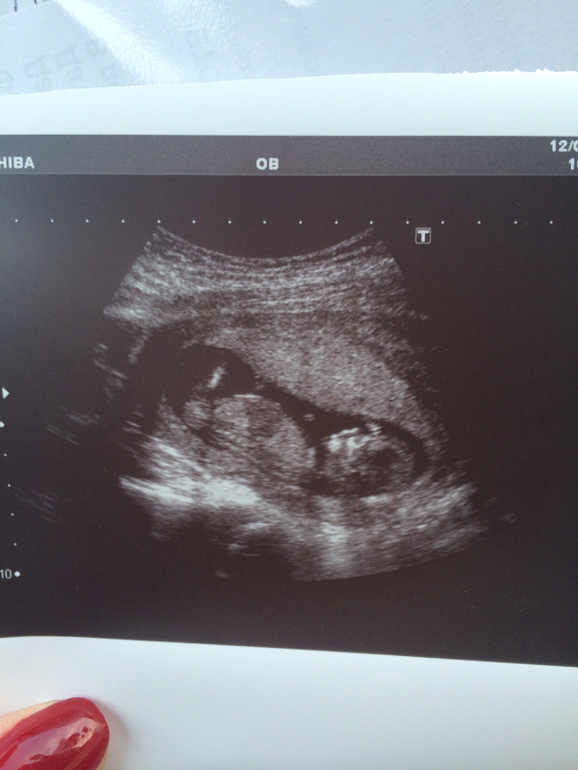

Узи планово надо было ждать - 2 недели, короче забила и сдала платно в "здоровом поколении" (стоить почти 6.000 - нехило так ), но зато быстро). Опоздала я...Срок уже 12, 1 акушерских, по узи - почти 14....Большой деть, надеюсь, что пацан) Жалко пол не увидели) Результаты крови отдали сразу, там все гут, кроме рисков по возрасту...но насколько он информативен на 14 неделях....Да из неприятного: тонус был приличный и деть был зажат (( но это могло быть следствием осмотра на кресле...А еще написали, что полное предлежание плаценты...Но как правило у всех поднимается потом, так узист сказал...Иначе ПКС

КТК у нас уже 71 мм....